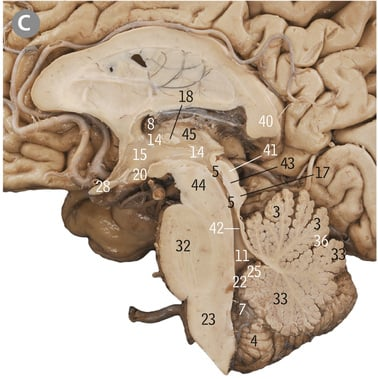

24

Midbrain

32

Pons

23

Medulla oblongata

What pathway is the inferior colliculus a part of?

Auditory pathway

What cortex does the inferior colliculus connect the inner ear to

Auditory cortex

17

Inferior colliculus

41

Superior colliculus

What is the superior colliculus play a key component in

Eye movements, visual processing and behaviour

5

Cerebral aqueduct

43

Tectum of midbrain

44

Tegmentum of midbrain

Is the tectum anterior or posterior to the cerebral aqueduct

Posterior

47

Trochlear nerve

Which part of the midbrain does the trochlear nerve exit from

Dorsal aspect of midbrain inferior to inferior colliculi

What is the site where the midbrain and pons are connected called

Pontomesencephalic junction

3

Dorsal median sulcus

4

4th/fourth ventricle

Floor of fourth ventricle

What forms the floor of the 4th ventricle

Medulla caudally, pons rostrally

What forms the roof/dorsal wall of the 4th ventricle

Cerebellar peduncles

Middle cerebellar peduncle

What is the 4th ventricle connected to the subarachnoid space of the cerebellopontine angle by?

Lateral aperture of 4th ventricles/Foramen of Luschka

X

Lateral aperture of 4th ventricle/foramen of luschka

Median aperture of 4th ventricle/foramen of magendie

What does the median aperture of the fourth ventricle connect the 4th ventricle to which part of the subarachnoid space?

Cisterna magna

2

What are the lateral walls of the rostral part of the 4th ventricle made up of?

Superior and inferior cerebellar peduncles

Superior cerebellar peduncle

Inferior cerebellar peduncle

In the rostral pons, where do the walls of the 4th ventricle converge at

What is the line referring to

8

Crus cerebri

What does the circled area refer to

Interpeduncular fossa

26

Oculomotor nerve

What are the nerve fibres descending through the crus cerebriÂ

Corticobulbar fibres, corticospinal fibres

What type of fibres are the corticobulbar fibres

Motor fibres